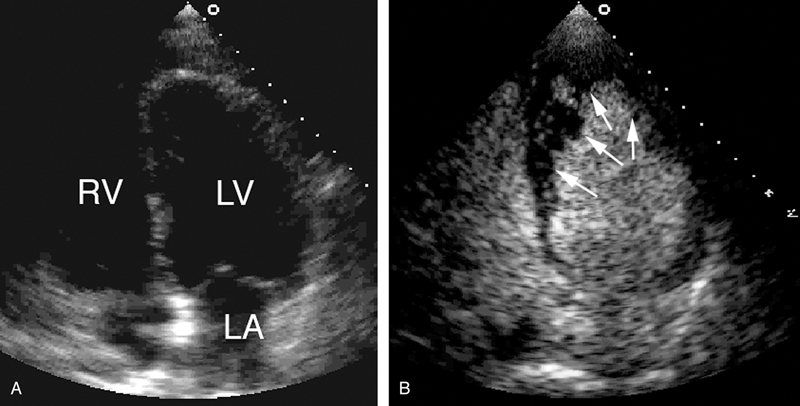

فحوصات تشخيصية لبعض امراض القلب والشرايين التاجية